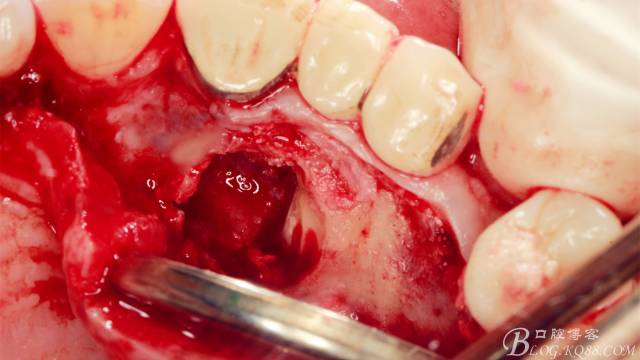

長柄裂鉆分離牙冠,微創(chuàng)挺插入后順時(shí)針或者逆時(shí)針輕擰一下,手上去感受牙冠斷開的那一瞬間,有時(shí)候耳朵也能聽見啪得一聲,不過此刻因?yàn)檠拦谥車墓亲枇?,牙冠是不能取出的?/p>

T形分牙,把牙冠分為兩瓣,減少阻力。

分別挺出兩瓣牙冠,可見牙根截?cái)嗝妗?/p>

微創(chuàng)挺直接挺出牙根。

取出牙根,清理創(chuàng)面。